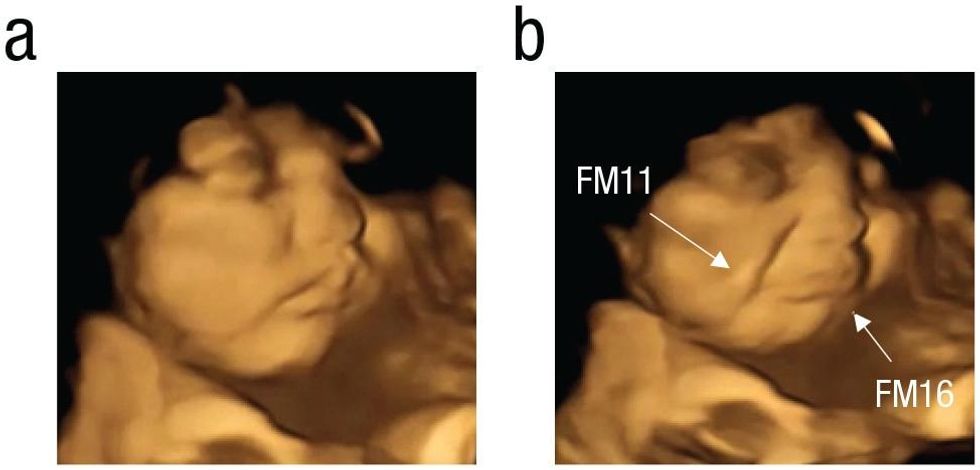

Scientists from the University of Durham used 4D ultrasound scans to see if foetuses could react to different flavours and found that the unborn babies made a cry-like face when exposed to the bitterness of kale.

Once a baseline was taken, one group ate a vegetable capsule of either carrot while the other ate a vegetable capsule of kale. Scientists then observed how foetuses facial expressions changed.

The carrot capsules led to laughter-face gestalt in foetuses.

The kale capsules led to cry-face gestalt.